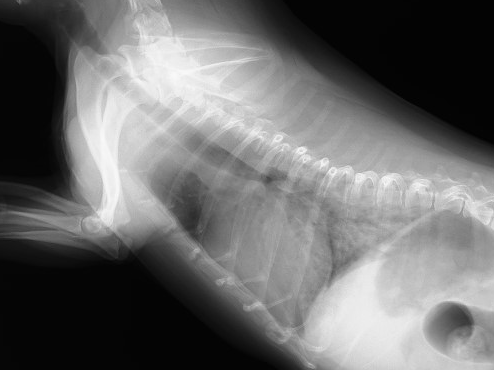

心臓のエコー検査では、僧帽弁が厚くビロビロになって閉鎖不全が生じているため、左心室から左心房の方に逆流する血流(青いところ)が認められます。この子は1日程度、酸素テント(ICU装置)で入院しながら、心臓の点滴を行うことで、心原性肺水腫が改善し、現在は内服薬で普段の生活に支障がない状態で管理できています。(5ヶ月後のレントゲン写真で肺水腫が改善し、心臓の肥大も改善しているのがわかります)